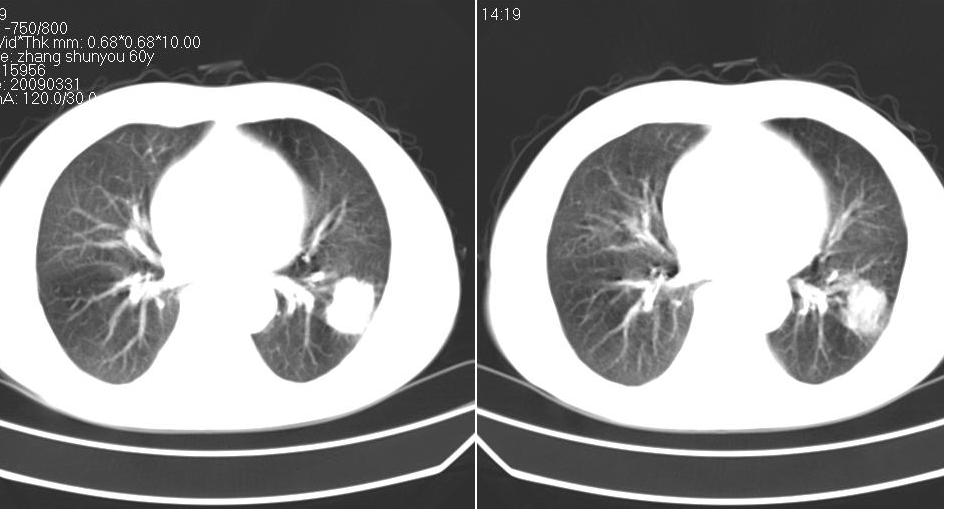

标题: CT19131:男 60岁,咳嗽,喀痰,胸闷,有吸烟史,胸部CT平扫 [打印本页]

男 60岁,咳嗽,喀痰,胸闷,有吸烟史,正常图片未上传,请谅解。

左肺肿块有分叶、有毛刺,符合周围型肺癌。

考虑左肺下叶周围型肺癌可能性大。

分叶状肿块,有毛刺,有晕,有粗纹理直通肺门,支持考虑周围型肺癌